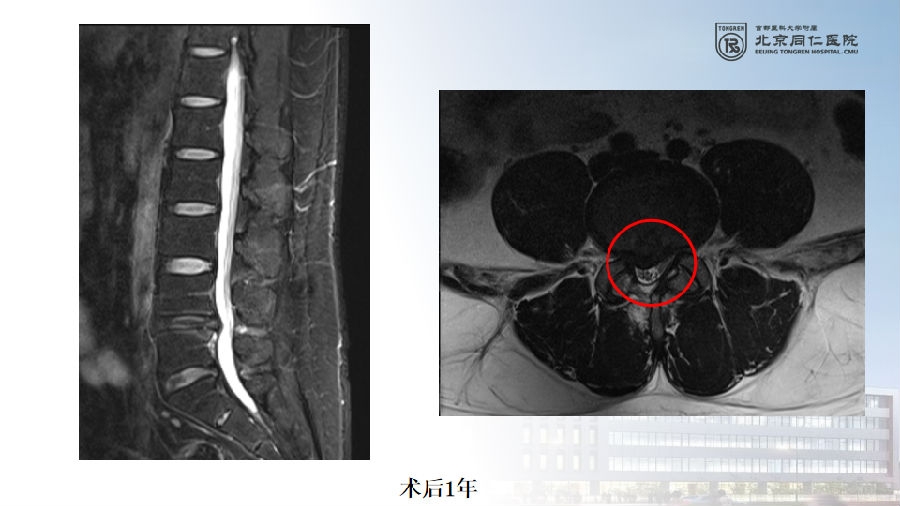

六、复发(2.27%)

病例(椎间盘突出复发)

女,42岁。

主诉:腰痛伴左下肢疼痛2月。

查体:疼痛放射至左侧臀部、大腿后侧、小腿后外侧。

思考和建议

完整切除突出的椎间盘

切除的椎间盘为影像学体积150%

视情况缝合纤维环,避免复发